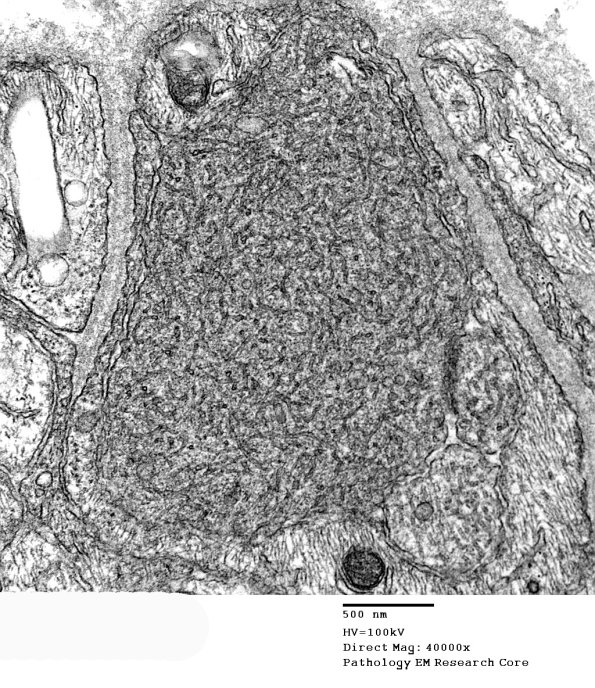

Classical dystrophic axon with tubulovesicular elements. (electron micrographs)